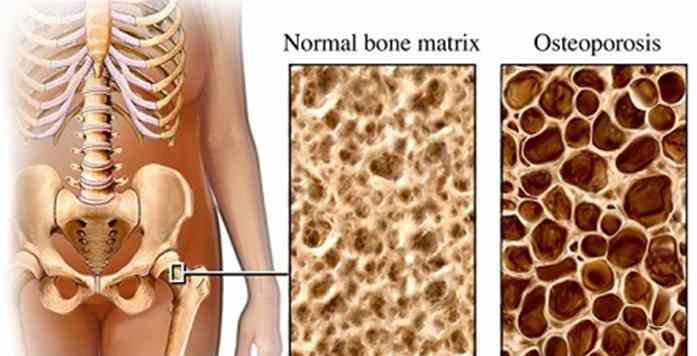

- Medical Devices and Biomedical Engineering